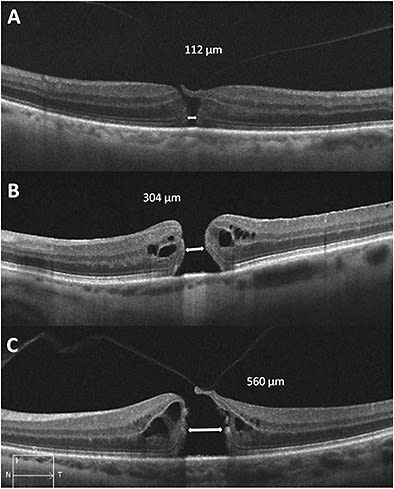

Aperture size is defined as the minimum width measured at the narrowest hole point in the mid-retina, a measurement drawn roughly parallel to the RPE.1 This aperture size is significant because it can be used to help predict anatomic success with both medication and surgery. In addition, FTMH can be subclassified based on whether or not VMT is present (Figure 2).

Figure 2. OCT scans illustrating examples of FTMH according to the IVTS classification system. A) Small FTMH with aperture size ≤250 µm. Note the overlying vitreous attachment. B) Medium FTMH with aperture size >250 µm and ≤400 µm. There is no associated vitreous attachment. C) Large FTMH with aperture size >400 µm. Persistent vitreous attachment is visible at the edge of the hole.

Finally, the term “idiopathic” has been abandoned, because it is clear that such holes are created by VMT. Holes resulting from VMT should be referred to as primary macular holes, while those that occur as a result of other processes (eg, trauma, macular telangiectasia type II) should be referred to as secondary macular holes.